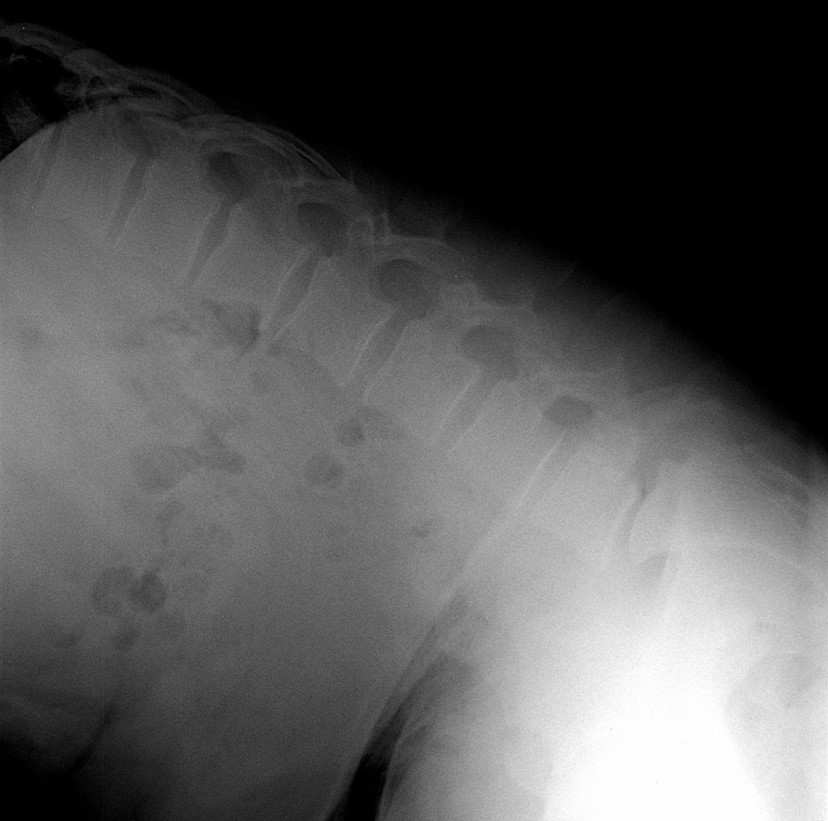

34 Yaşında Erkek Hasta

Low back pain

ODİ: %16

RM: 5/24

Ameliyat Öncesi